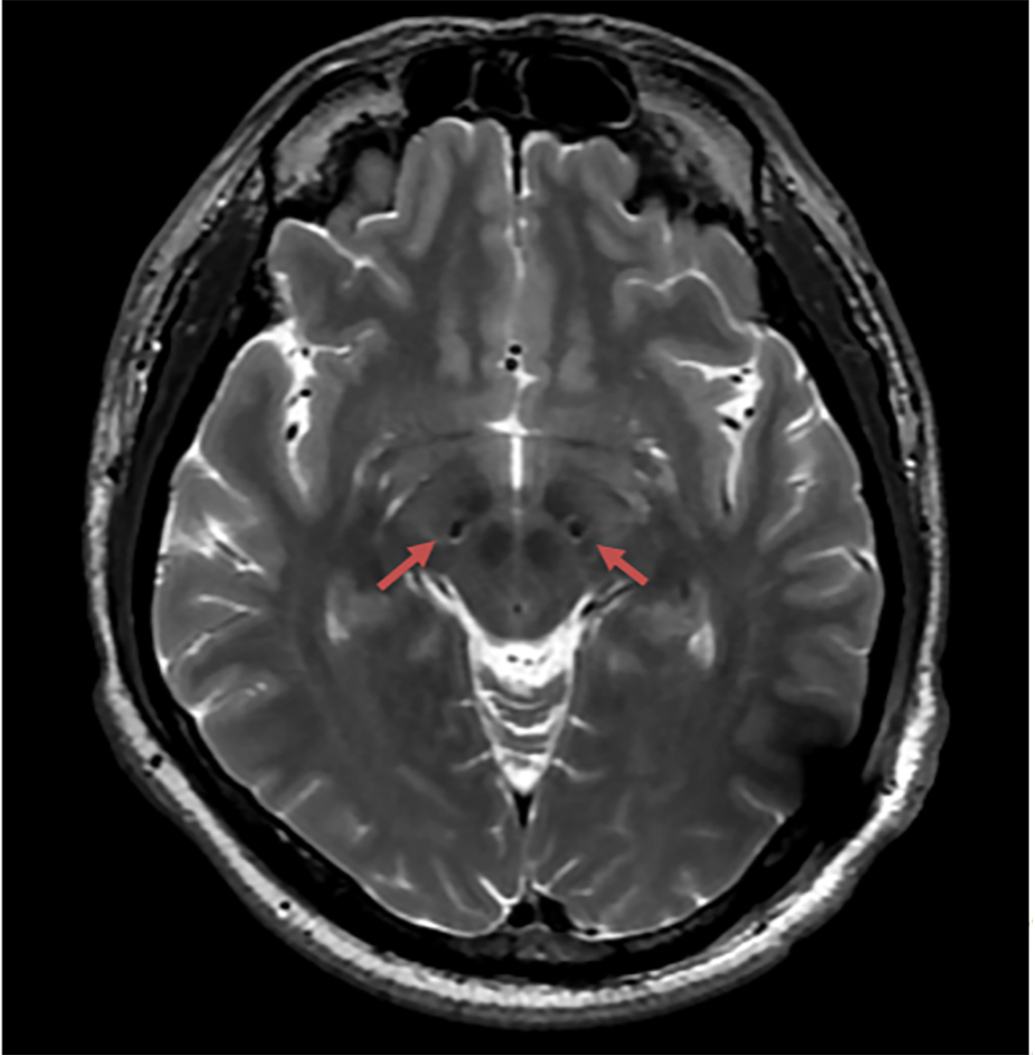

在手术中,周洪语带领的神经外科功能团队和影像科、麻醉科专家密切配合,电极精准植入患者体内。术后复查,电极位置精准。

患者术后复查,提示电极位置精准。 上海交通大学医学院附属仁济医院 供图